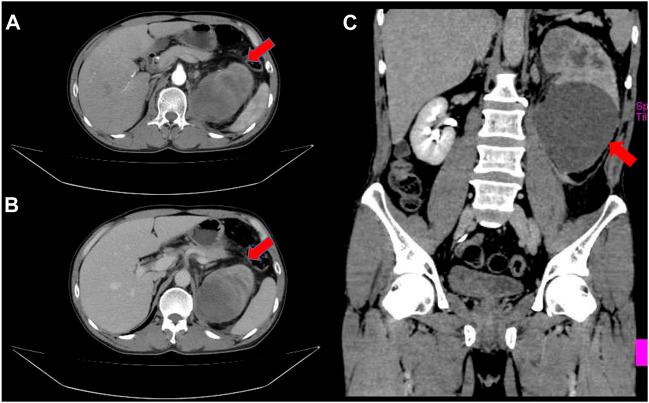

We report a rare case of urothelial carcinoma (UC) of the renal pelvis with trophoblastic differentiation that occurred in a 55-year-old male patient. The patient presented with gross hematuria and paroxysmal lumbago pain 5 months ago. The enhanced computed tomography (CT) scan demonstrated a large space occupying lesion in the left kidney and multiple retroperitoneal lymph node enlargements. Histologically, high-grade infiltrating urothelial carcinoma (HGUC) contained giant cells which were positive for beta-human chorionic gonadotropin (β-hCG). Three weeks after resection, positron emission tomography and computed tomography (PET-CT) scan showed multiple nodules of metastasis in the left renal region, extensive systemic muscle, bone, lymph node, liver and bilateral lung metastases. The patient underwent bladder perfusion chemotherapy and gemcitabine combined with cisplatin chemotherapy regimens. This is the eighth documented case of UC of the renal pelvis with trophoblastic differentiation. Due to its rarity and extremely poor prognosis, it is important to clarify the characteristics of the disease and make an accurate and prompt diagnosis.

我们报告了一例罕见的肾盂尿路上皮癌(UC)伴滋养细胞分化,发生在一名 55 岁男性患者中。该患者 5 个月前出现肉眼血尿和阵发性腰痛。增强计算机断层扫描(CT)显示左肾有一个大的占位性病变和多个腹膜后淋巴结肿大。组织学上,高级别浸润性尿路上皮癌(HGUC)含有β-人绒毛膜促性腺激素(β-hCG)阳性的巨细胞。切除后 3 周,正电子发射断层扫描和计算机断层扫描(PET-CT)显示左肾区、广泛全身肌肉、骨骼、淋巴结、肝脏和双侧肺转移有多个结节。患者接受了膀胱灌注化疗和吉西他滨联合顺铂化疗方案。这是第 8 例有报道的肾盂尿路上皮癌伴滋养细胞分化。由于其罕见性和极差的预后,明确疾病的特征并做出准确和及时的诊断非常重要。